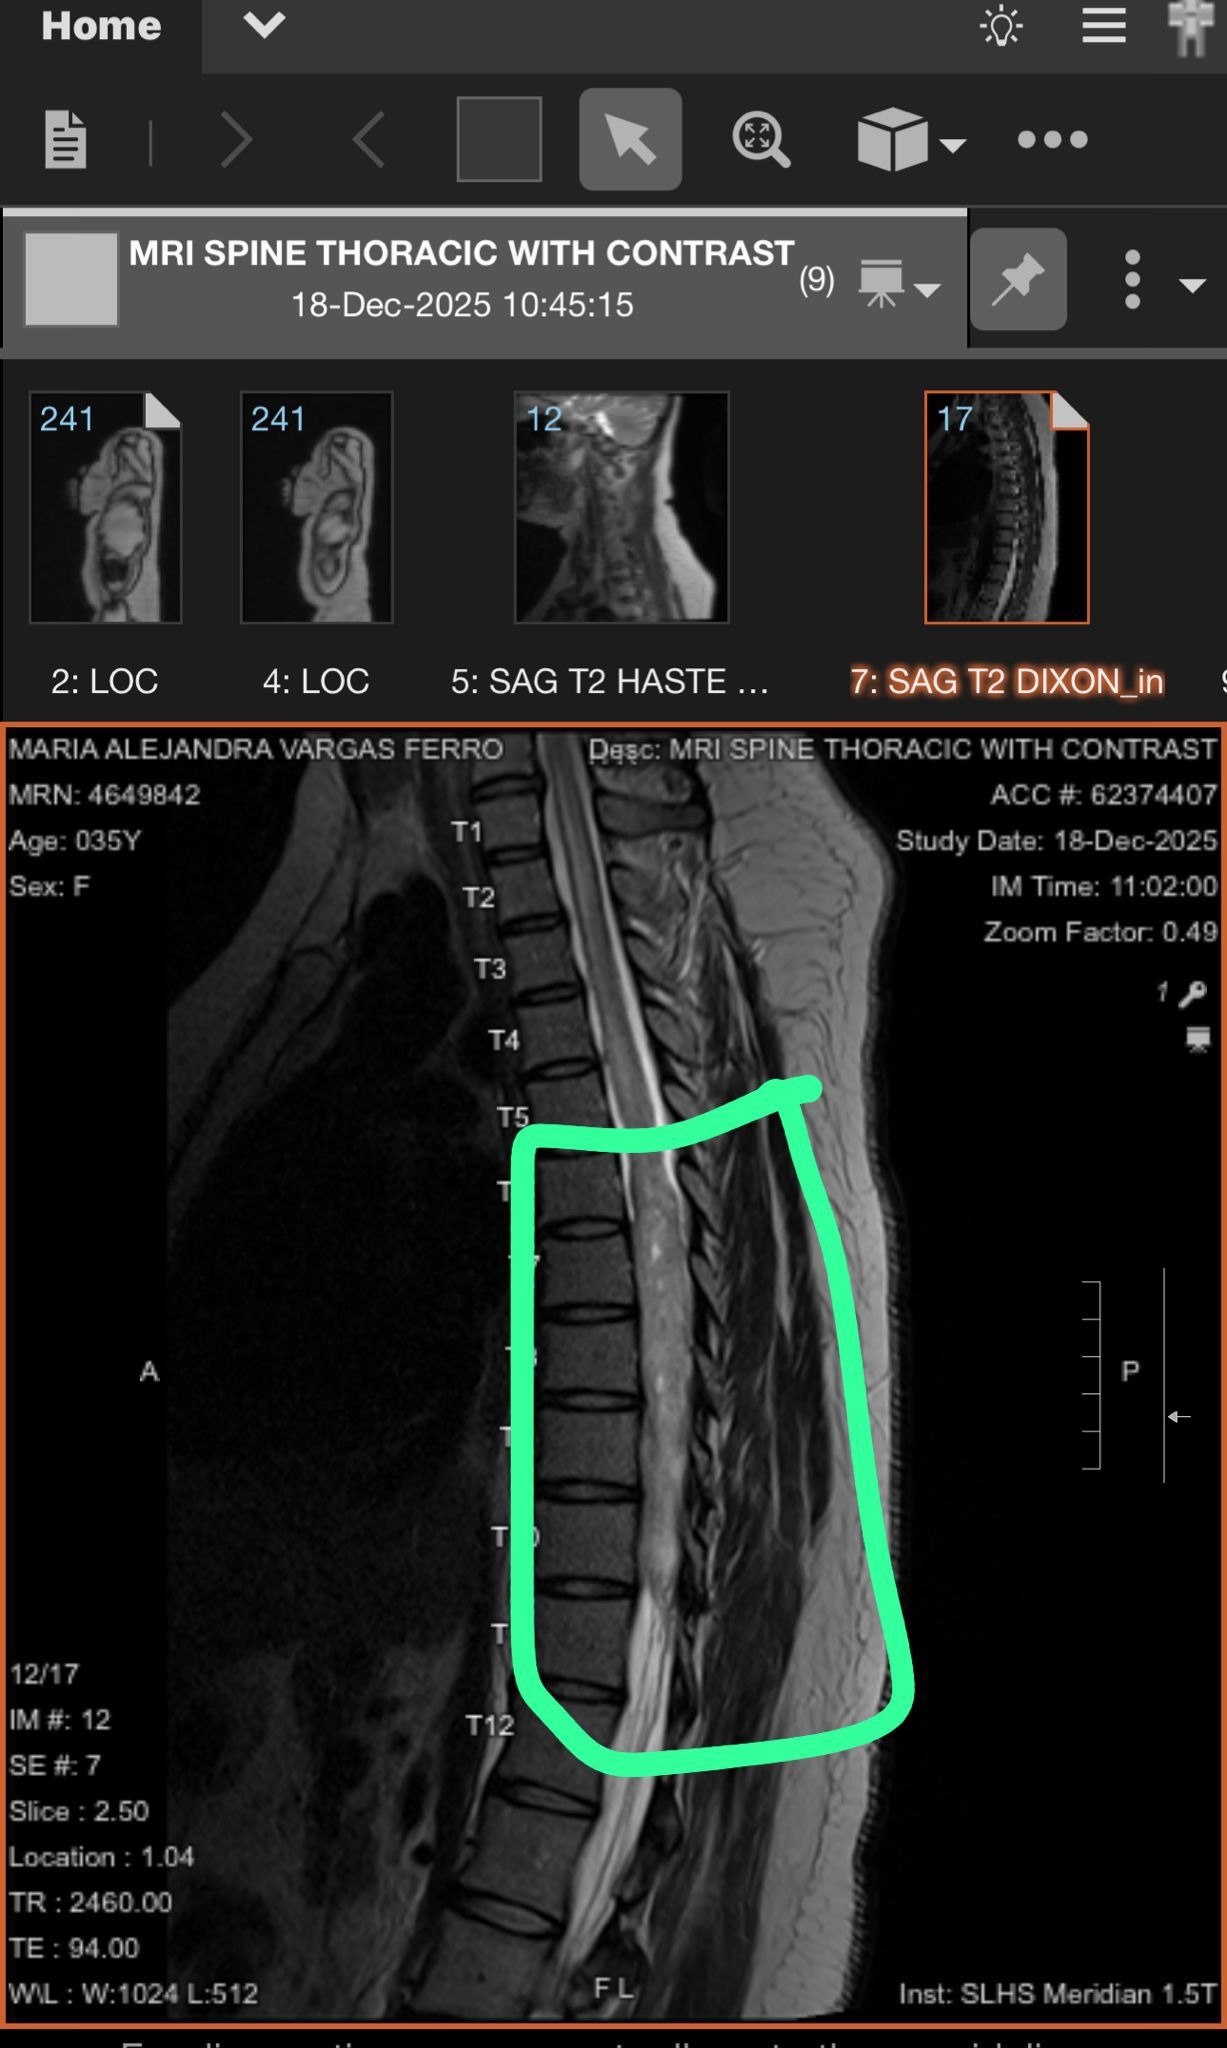

Recently, Alejandra received devastating news: she was diagnosed with a tumoral lesion in her spinal cord. The surgery she needs to survive isn’t available in Idaho, so she must travel to Utah for the procedure. With her diagnosis, Alejandra can no longer work, and the medical bills are piling up quickly. The stress of her illness, combined with the financial burden, has been overwhelming for both Alejandra and Valentina.

Recently, Alejandra received devastating news: she was diagnosed with a tumoral lesion in her spinal cord. The surgery she needs to survive isn’t available in Idaho, so she must travel to Utah for the procedure. With her diagnosis, Alejandra can no longer work, and the medical bills are piling up quickly. The stress of her illness, combined with the financial burden, has been overwhelming for both Alejandra and Valentina.